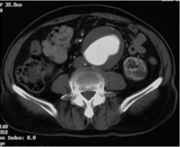

腹部大動脈瘤 (AAA) は、血液を心臓から体の残りの部分に移動させる主要な動脈、つまり大動脈の膨らみです。胴体を通って流れ、肝臓や腎臓などの臓器に血液を供給します。

この血管は2つに分かれて足まで伸びます。 AAA は、大動脈が分割される直前の部分で発生します。

AAA をスクリーニングするために、医師は次のような医用画像技術を使用します。

- CT スキャン:このスキャンでは、X 線によって AAA の詳細な画像が作成されます。